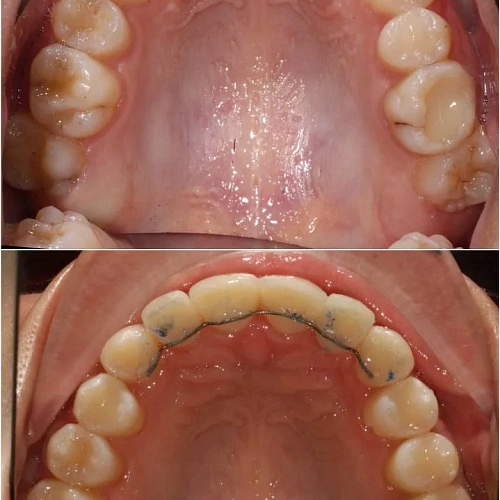

Проблема: В клинику обратилась пациентка — беспокоили неровные зубы и неправильное смыкание. Зубные ряды сходились некорректно, зубы стояли со смещением, что влияло и на внешний вид, и на распределение нагрузки при жевании.

Решение: Поставили элайнеры 3D Smile на обе челюсти. Лечение заняло 4 года и потребовало нескольких последовательных этапов коррекции. Капы менялись каждые 1–2 недели, на контрольных визитах отслеживали прогресс и выдавали новые наборы. Зубы встали в правильное положение, смыкание нормализовалось. Зафиксировали ретейнеры на обе челюсти, изготовили ретенционные капы. Пациентка прошла онлайн-консультацию с ортопедом для оценки дальнейших шагов.

Лечение потребовало нескольких последовательных этапов — каждый дозаказ кап уточнял положение зубов, которые не полностью отреагировали на предыдущий курс. Элайнеры 3D Smile позволяют работать поэтапно, корректируя план по ходу. Результат получен, ретейнеры зафиксированы. Рекомендовала пациентке консультацию ортопеда для оценки состояния зубов после лечения